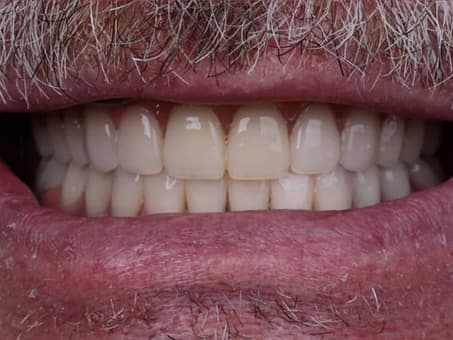

Зубные имплантаты полностью повторяют физиологическое строение и внешний вид зубов пациента, не отличаясь от них ни блеском, ни прозрачностью, и превосходя их по прочности.

Коронковая часть изготавливается из экологически безопасного диоксида циркония, который на сегодняшний день является лучшим материалом для протезирования.

После приживления импланта наступает второй этап — установка постоянной коронки. Сначала врач делает оттиски или 3D-скан, на основе которых в зуботехнической лаборатории изготавливается индивидуальный протез.

Конструкция на циркониевых коронках является самым современным и эстетичным решением. Диоксид циркония прочен, не вызывает аллергию и внешне неотличим от настоящих зубов. Такая коронка точно повторяет форму и цвет зуба, выдерживает жевательную нагрузку и служит десятилетиями.

Если вы испытываете смущение и раздражение от того, что у вас отсутствует зуб или несколько зубов, если вы устали носить громоздкие зубные протезы или страдаете от старых методов протезирования, то спасением для Вас будет современный метод восстановления с использованием имплантантов. Отзывы тех кто прошел через данную операцию подтверждают: имплантация зубов это надёжное и эффективное решение на долгие десятилетия.

Наши работы